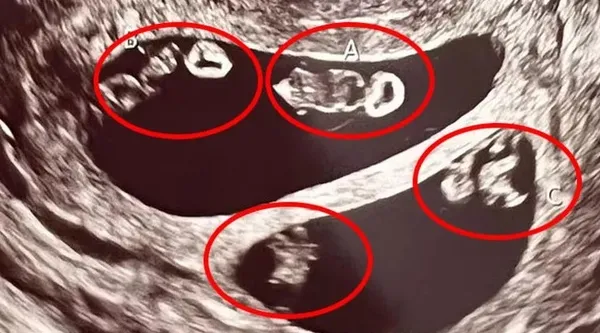

Ashley, 2 hafta sonra 47 yaşındaki erkek arkadaşı Val ile beraber ultrason kontrolüne gittiğinde sevinci büyük şoka dönüştü ve bir değil tam dört bebeğe hamile olduğunu öğrendi.

Daha önceki ilişkisinden de bir kızı olan Anne Adayı karnındaki dört bebeğin dördüz değil iki ayrı tek yumurta ikizi olduğunu öğrendi.

Bu keşfin ultrason teknisyenini bile şoke ettiğini anlatan anne adayı, "Taramayı ilk başlattığı zaman ekrana baktı ve 'A,B' yazdı. Durup bir an ona baktım. Görünen o ki ikizlerim olacaktı." diye sözlerine başladı ve şöyle devam etti;

"Teknisyenin kafasının karıştığını görebiliyordum. Ekranda gördüğü şeyin gerçek olup olmadığını anlamak için odadan çıkmak zorunda kaldı. Döndüğünde ise bana inanılmaz durumu anlattı. Dört bebeğe hamileydim. İki kız ve iki erkek."

ABC News'de yer alan habere göre aynı anda çift ikiz bebeğe sahip olmak nadir görülse bile mümkün. Ashley'in yumurtalarından her ikisi de bölünmeden önce aynı anda döllendi, bu da onun iki ayrı tek yumurta ikizine hamile kalmasına neden oldu.